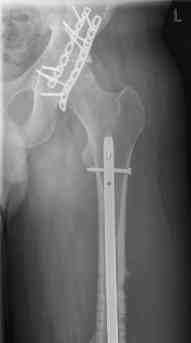

16 yr old boy, high energy motorcycle trauma trauma in July 2005 with:

- hip dislocation + acetabular fracture L

- distal femoral fracture L

- tibial shaft fracture L

- metatarsal fractures L

july 05: LISS femur, LCP plate tibia, double recon. plate post. acetabulum

feb 07: retrograde nail + bone graft + BMP

may 07: dynamisation nail

sept 07: locking screw removal (max. dynamisation reached)

nov 07: persistant non-union distal femur; other fractures healed uneventfully.

All with gradual/partial weightbearing etc. Currently 50-100% weight bearing, no pain.

Soft tissues are intact. No smoking or diabetes.CRP <2